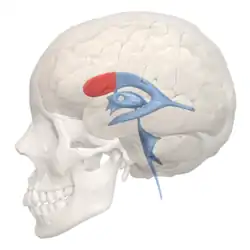

Position of lateral ventricles (shown in red)

Position of lateral ventricles (shown in red) -